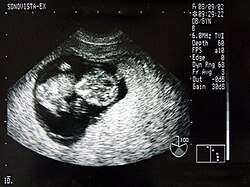

Ein wesentlicher Vorteil der Sonografie gegenüber dem in der Medizin ebenfalls häufig verwendeten Röntgen liegt in der Unschädlichkeit der eingesetzten Schallwellen. Auch sensible Gewebe wie bei Ungeborenen werden nicht beschädigt, die Untersuchung verläuft schmerzfrei.

Neben der Herztonwehenschreibung (Kardiotokografie) ist sie ein Standardverfahren in der Schwangerschaftsvorsorge. Eine spezielle Untersuchung der Pränataldiagnostik zur Erkennung von Entwicklungsstörungen und körperlichen Besonderheiten ist der Feinultraschall.

Von den Monitorbildern werden zur Dokumentation Ausdrucke, sogenannte Sonogramme, oder gelegentlich Videoaufnahmen gemacht. Schwangeren wird häufig auch ein Bild ihres ungeborenen Kindes überlassen.